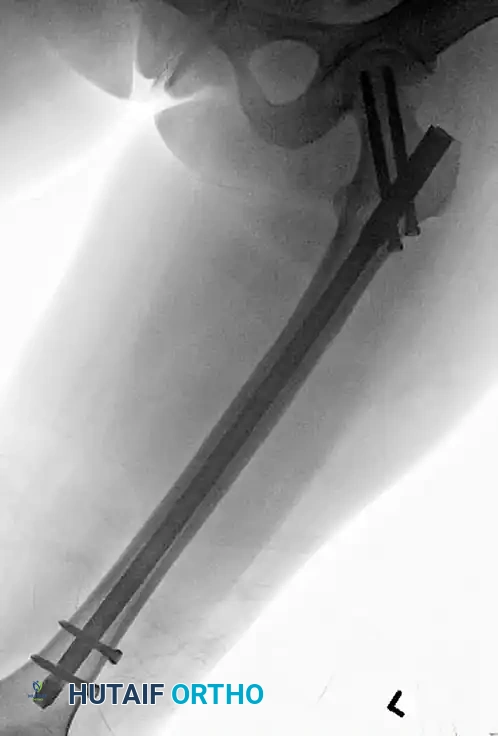

2. Plate Introduction and Provisional Fixation

Once appropriate alignment has been achieved, introduce the proximal femoral locking plate through the proximal wound. Slide it submuscularly along the lateral cortex of the femoral shaft.

- Position the plate at a level that allows the placement of a guide pin just proximal to the calcar femorale.

- We generally use a long plate that allows the placement of four or five well-spaced screws in the distal segment, adhering to the principle of low screw density to increase the working length of the construct.

- Pin the plate in place proximally and distally with provisional K-wires or olive wires.